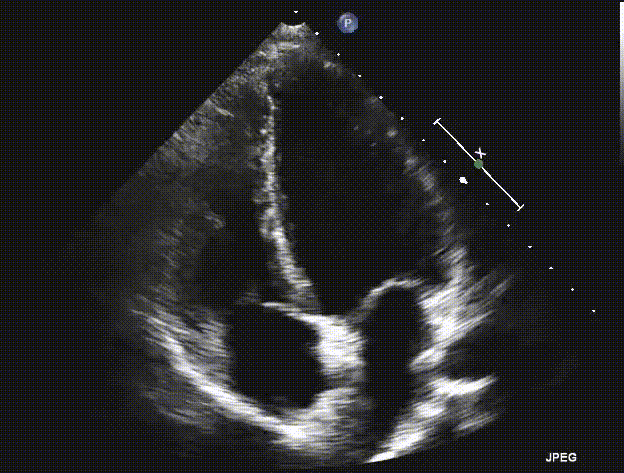

Identify this view.

RV focused apical 4C.